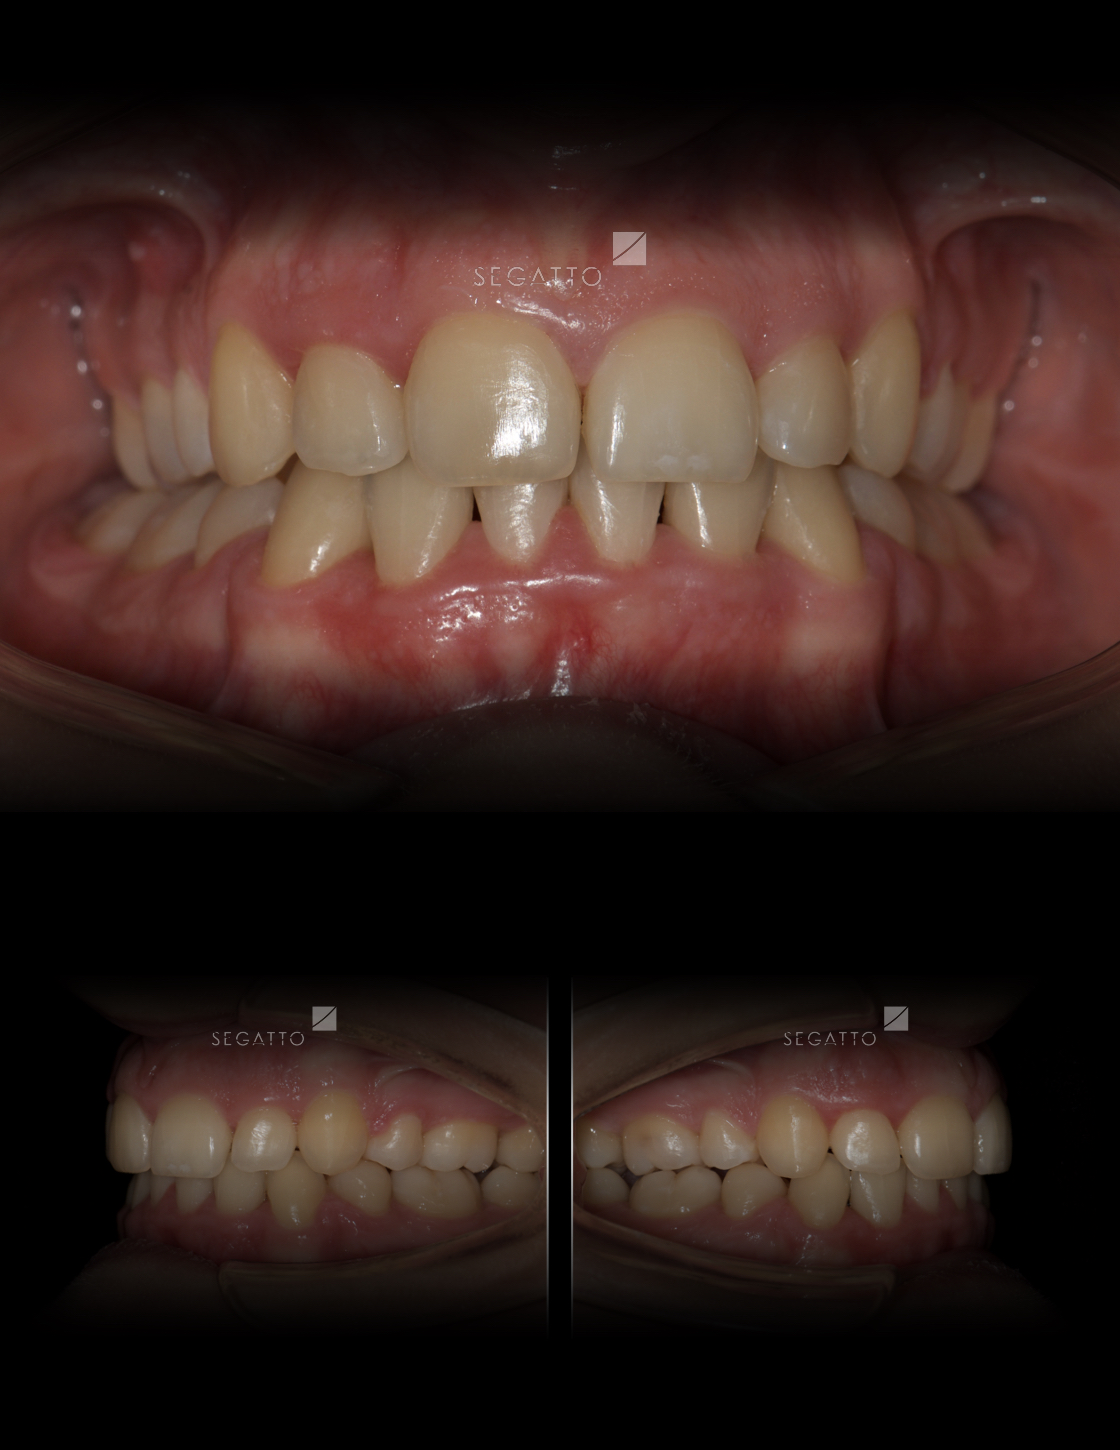

Orthodontics

Cases